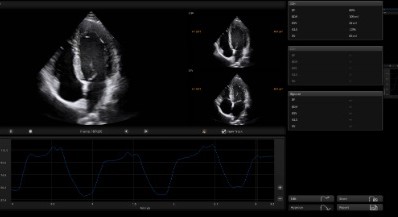

Auto EF

Cardiac function evaluation requires accuracy and speed as various calculations needs to be made. Auto EF, based on speckle tracking technology, acquires 2D EF and volumes within streamlined workflow.